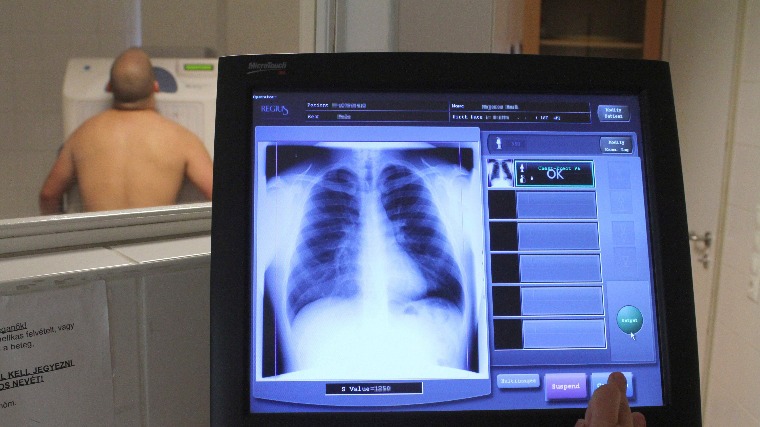

A Mátrai Gyógyintézet mozgó szűrőállomásával egész nap, 9:00–17:00 óra között tüdőszűrést végeznek.